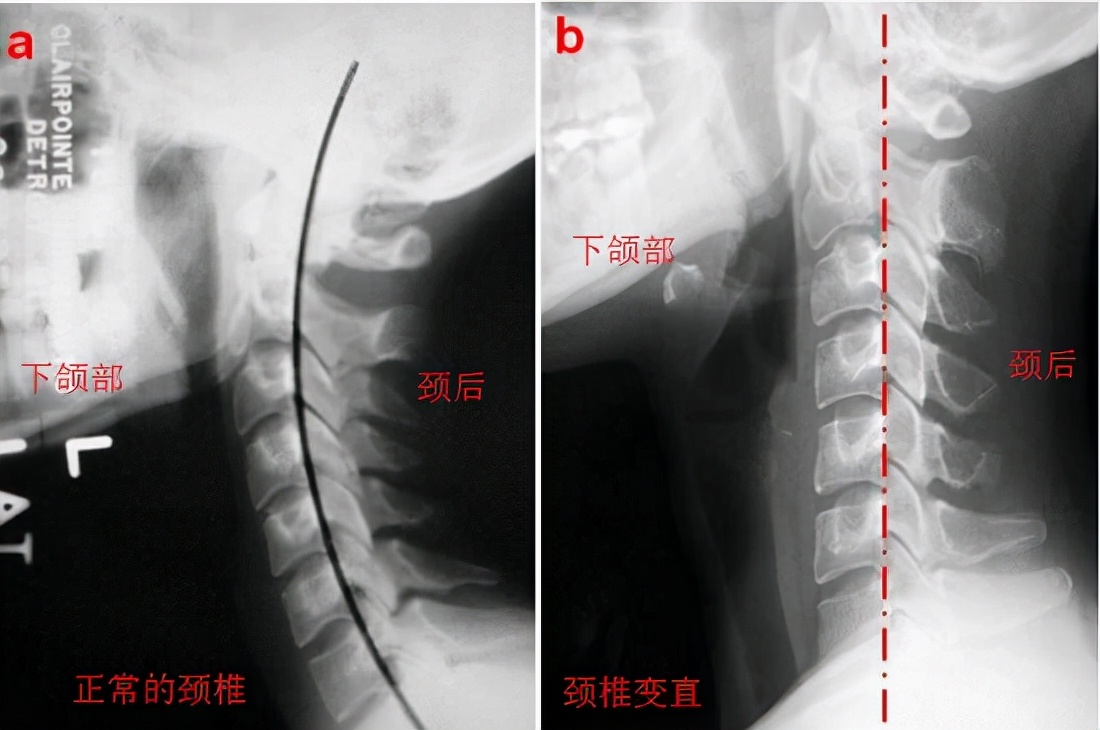

颈椎间盘突出的康复手段 下面重点讲讲牵引、按摩及运动疗法,另外再讲一个枕头和日常姿势调整的问题。1、大多数情况下,牵引对于椎间盘膨出和轻度的突出都是有效的。但必须要注意,比较显著的突出或脱出,牵引治疗的效果很差;另外,椎动脉型、交感神经型、脊髓型颈椎病的牵引要慎之又慎;损伤急性期也不应该进行牵引。牵引的作用是被动地将颈椎“提”起来,让拥堵的椎管具有更大的空间,并通过拉直后纵韧带所产生的张力让轻微突出或膨出的髓核还纳,还可以改善椎间小关节及诸多软组织的活动度,对于疼痛的改善也有效果。因此,符合牵引治疗适应证的情况下,还是非常有必要的。2、按摩的重点是颈后及肩后的肌肉,有痛感和酸胀感的部位是重点,可以在同一个部位持续按压,直到疼痛减轻或消失;然后就是斜方肌上束、肩胛提肌这两个重点肌群的按摩。